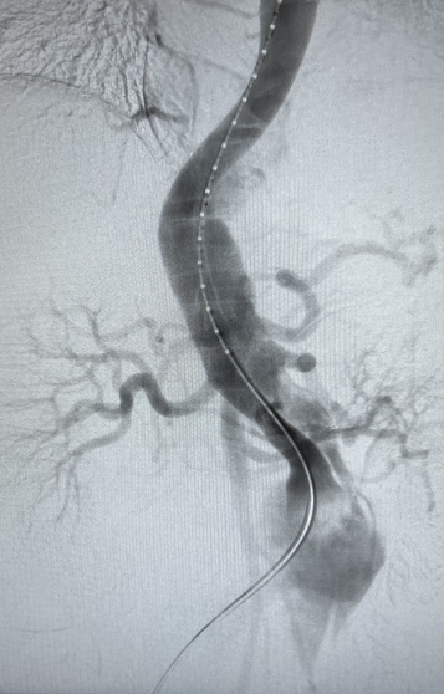

患者男性,51岁,主动脉夹层,通过Futhrough系统完成左锁骨下动脉(LSA)原位开窗重建。术中使用可调弯鞘(Fustar)和破膜系统,DSA显示破膜即刻成功,术后分支通畅,无并发症。

术前造影

穿刺破膜

球囊后扩

术后造影